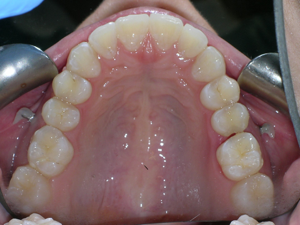

Here are the results. We used a bonded retainer on the bottom teeth.